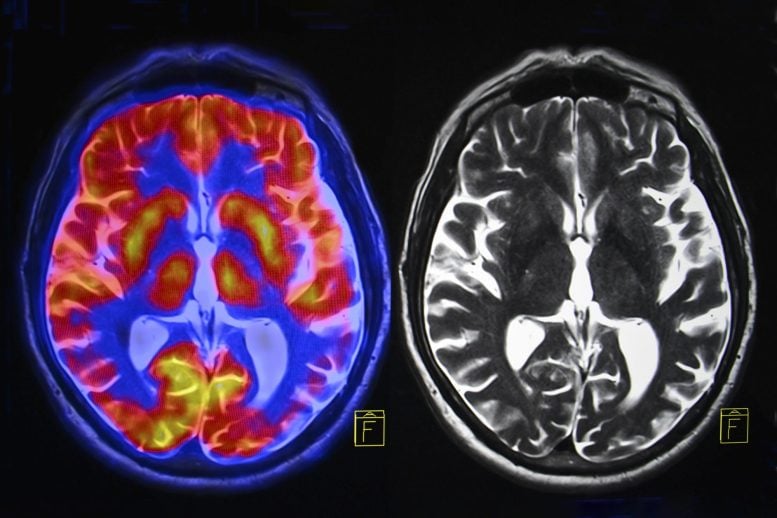

New analysis suggests menopause is related to mind quantity loss in key areas tied to reminiscence and feelings, together with larger charges of hysteria, melancholy, and sleep points. Hormone remedy didn’t forestall these modifications, although it might sluggish age-related declines in response pace. Menopause Linked to Mind Adjustments and Psychological Well being Challenges New analysis from […]